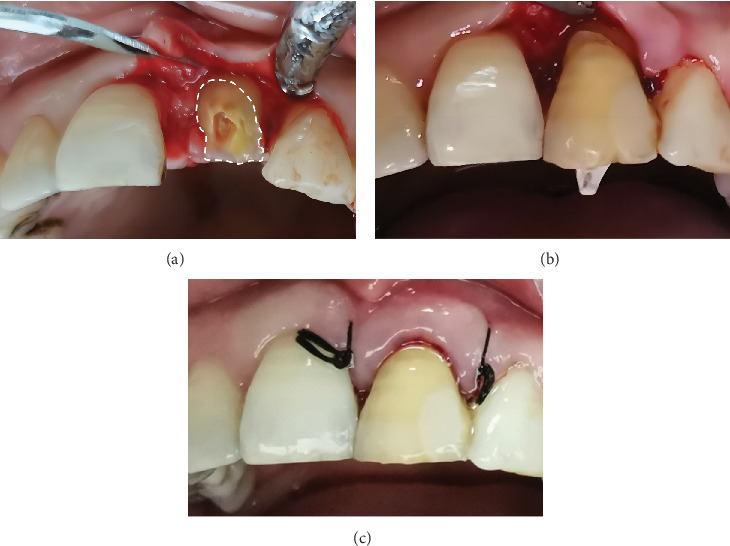

Crown-root fragment reattachment is an efficient method for restoring fractured teeth but is prone to failure due to complications such as microleakage or improper alignment, particularly when moisture control is compromised. In this case, the maxillary left central incisor that had sustained a complicated crown-root fracture was successfully reattached through a meticulously planned adhesive protocol. Specifically, precise visual reattachment on a small periodontal flap using the Super-Bond adhesive system in a controlled moisture led to favorable long-term results. The 55-month follow-up shows that conservative reattachment can restore function and appearance and preserve periodontal health.